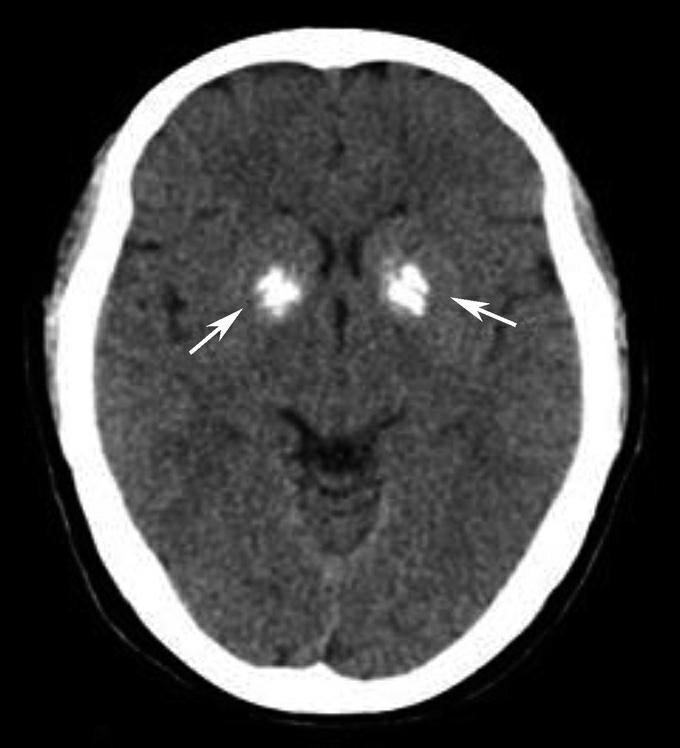

松果体、苍白球在成人期常出现钙化,属生理性钙化,一般无病理意义。需注意勿误诊为出血灶,尤其是单侧苍白球钙化时(图1-2-28)。

图1-2-28 苍白球生理性钙化

A.双侧苍白球对称性钙化,呈高密度影(箭);B.左侧苍白球钙化(箭),右侧苍白球钙化不明显